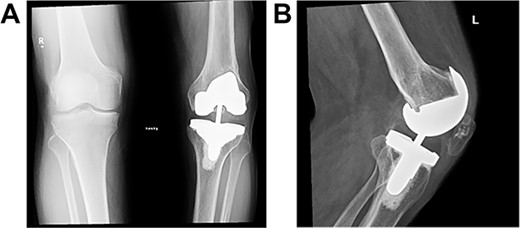

Post-operative plain radiographs from follow-up visits; (A) 3-month post-operative AP radiograph showing implant in place with a lateral gap sized to be 3.2 cm; (B) 3-month post-operative lateral radiograph of the knee showing implant in a satisfactory position.